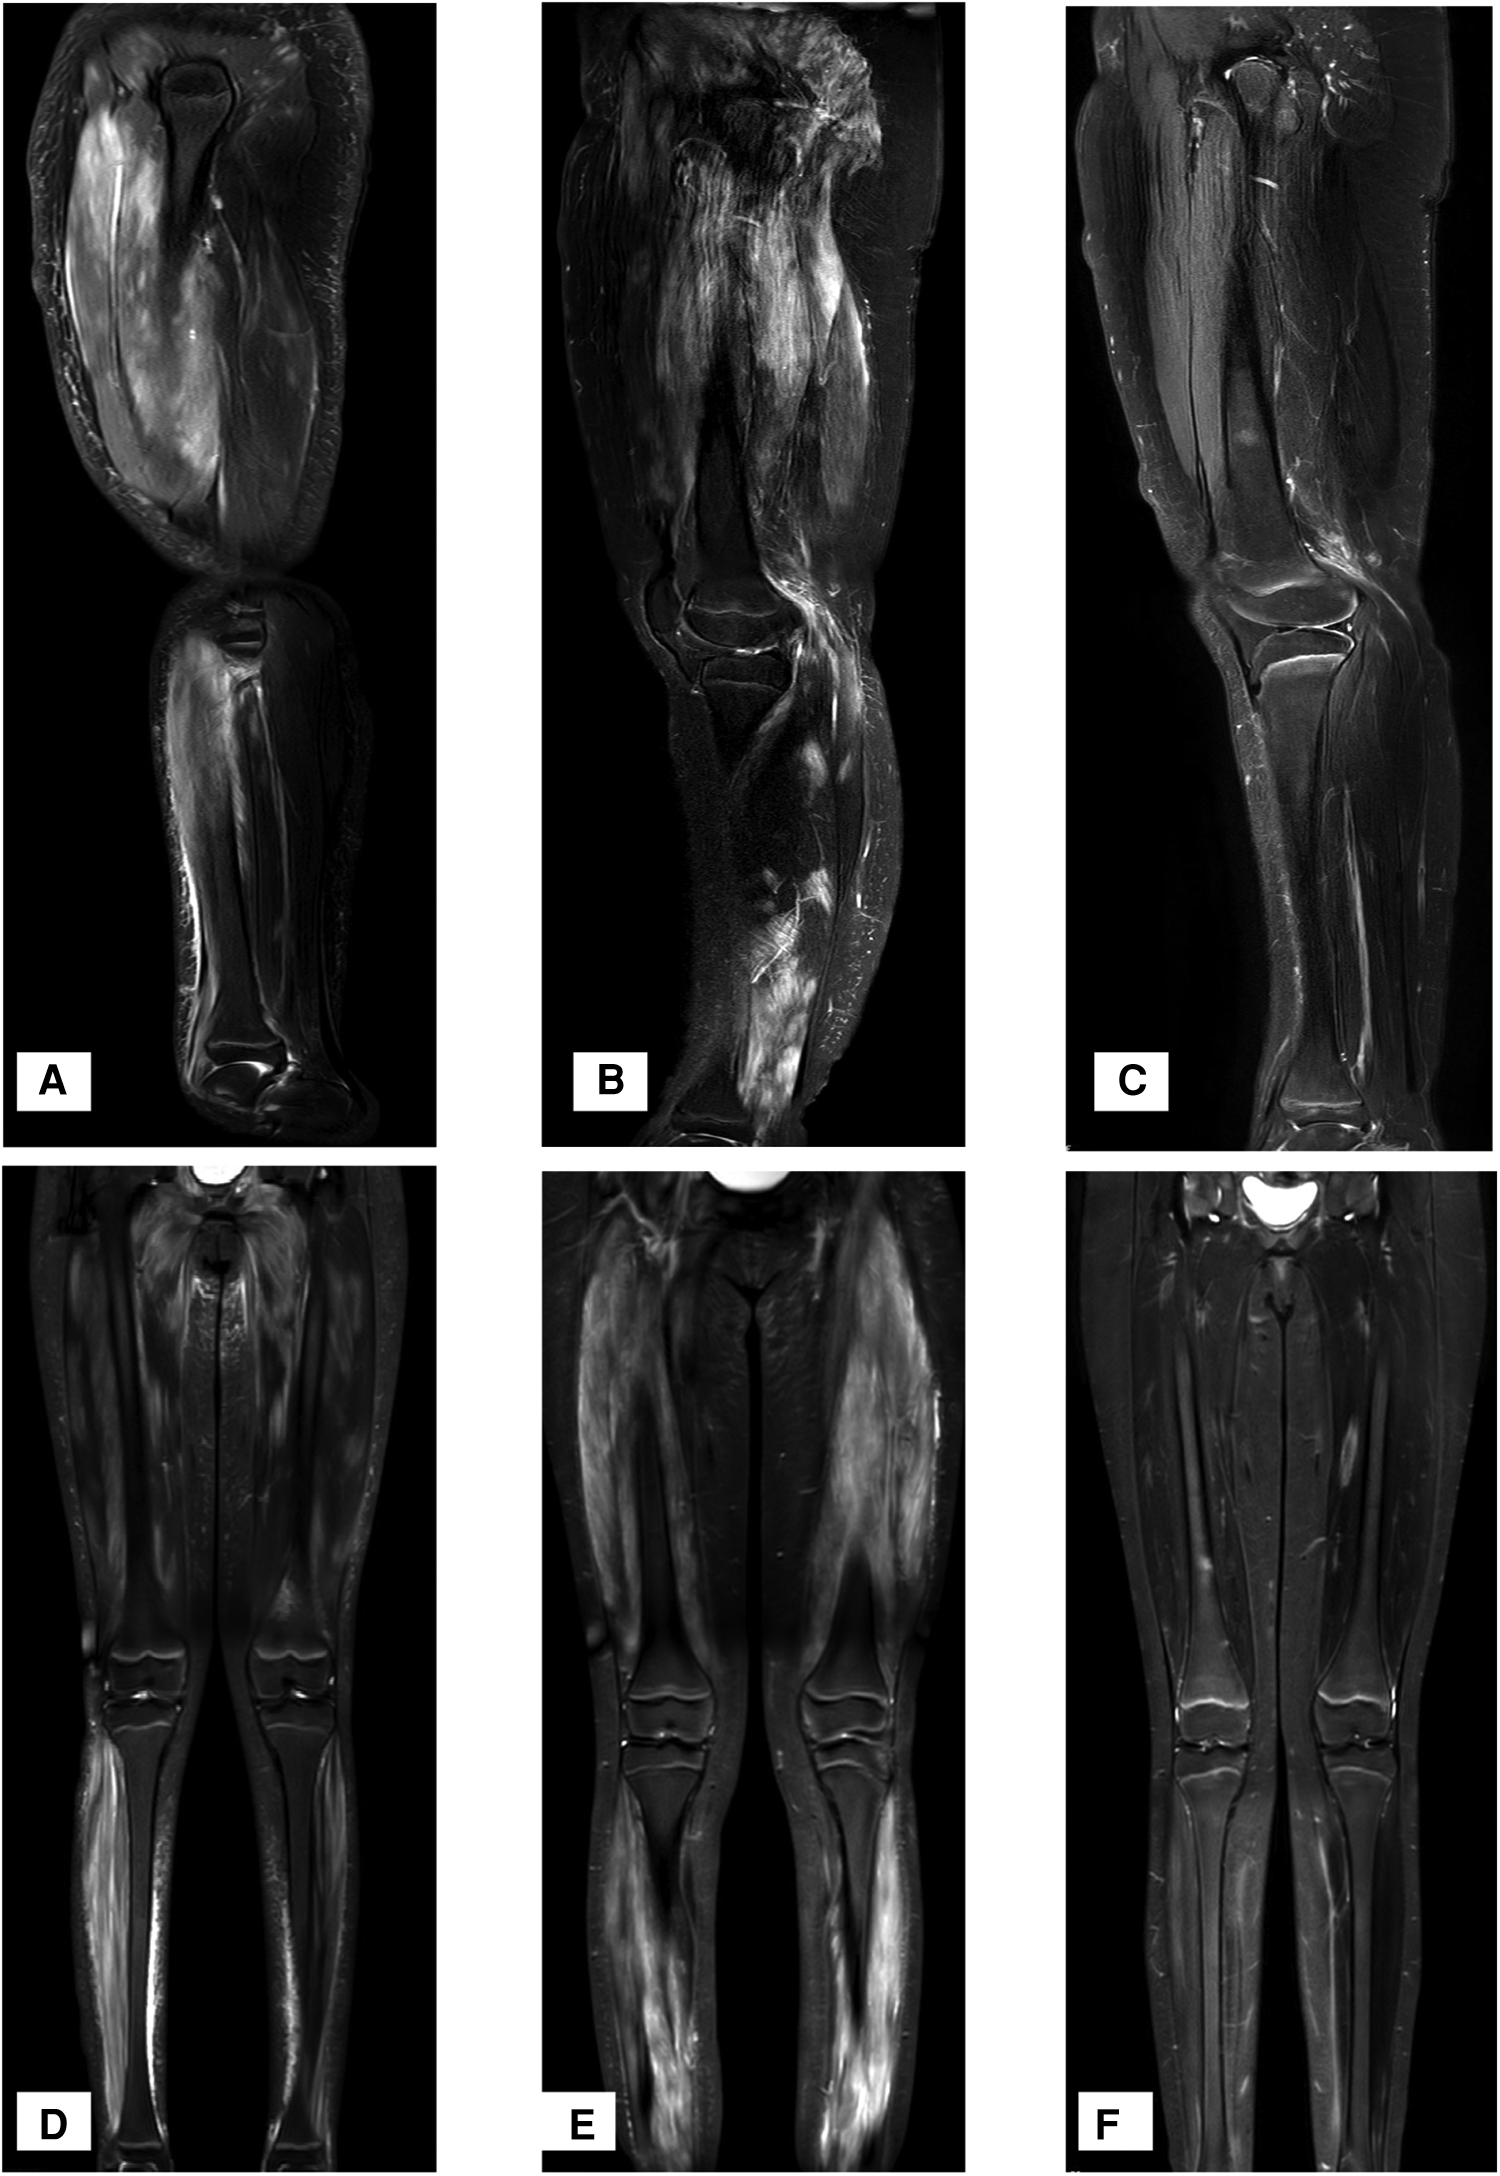

Laboratory tests found that the girl had elevated creatine kinase (CK) and lactate dehydrogenase (LDH), massive proteinuria, decreased albumin and elevated cholesterol, as shown in Table 1. ANA, anti-DsDNA, anti-ENA, ANCA, anti-GBM, CMV-Ab, HCV-Ab, HBS-Ag, and HSV-DNA were negative. The urinary system and abdomen ultrasound and chest computed tomography scan did not show any abnormalities. Electromyogram showed narrowed motor unit potentials, polyphase potentials, increased irregular waves and recruitment potentials. Magnetic resonance imaging (MRI) showed high signals on T2-weighted and Stir images of the legs and no rhabdomyolysis or muscle necrosis, as shown in Figures 1A,D.

Figure 1

MRI T2W and stir-weighted images of the muscles at the time of onset. (A,D) T2W and Stir images at the time of onset, showing a high signal on T2-weighted and Stir images. (B,E) T2W and Stir images at the time of recurrence, showing extensive muscle damage. (C,F) T2W and Stir images one year after the application of Adalimumab.

Twenty-one months later, the doses of MP and MMF were gradually reduced, and the skin rash and muscle weakness recurred. The 24 h urine protein was 227 mg (5.53 mg/m2/h, body weight 58 kg). MRI revealed extensive muscle damage and high signals in the muscles of the lower limbs, buttocks and pelvis in T2-weighted and Stir images (Figures 1B,E). The MP dosage was adjusted to 32 mg/day, and 40 mg adalimumab was subcutaneously injected every two weeks. The muscle strength of her limbs improved. MRI T2W and Stir-weighted images of the legs revealed decreased muscle damage one year after relapse (Figures 1C,F). Adalimumab was subcutaneously injected at 40 mg every two weeks for a total of 10 months and then every month for 5 months without side effects. The dosages of MMF and MP were decreased to 0.125 g and 2 mg per day, respectively.